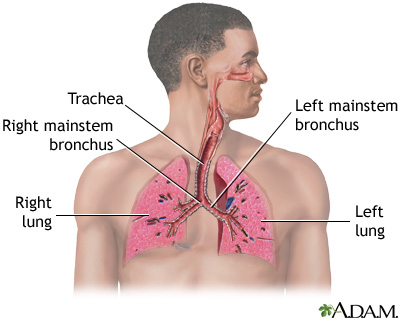

Pulmonary tuberculosis (TB) is a contagious bacterial infection that involves the lungs. It may spread to other organs.

Pulmonary TB is caused by the bacterium Mycobacterium tuberculosis (M tuberculosis). TB is contagious. This means the bacteria may spread from an infected person to someone else. You can get TB by breathing in air droplets from a cough or sneeze of an infected person. The resulting lung infection is called primary TB.

The primary stage of TB does not cause symptoms. When symptoms of pulmonary TB occur, they can include:

- Breathing difficulty

- Chest pain

- Cough (usually with mucus)

- Coughing up blood

- Wheezing